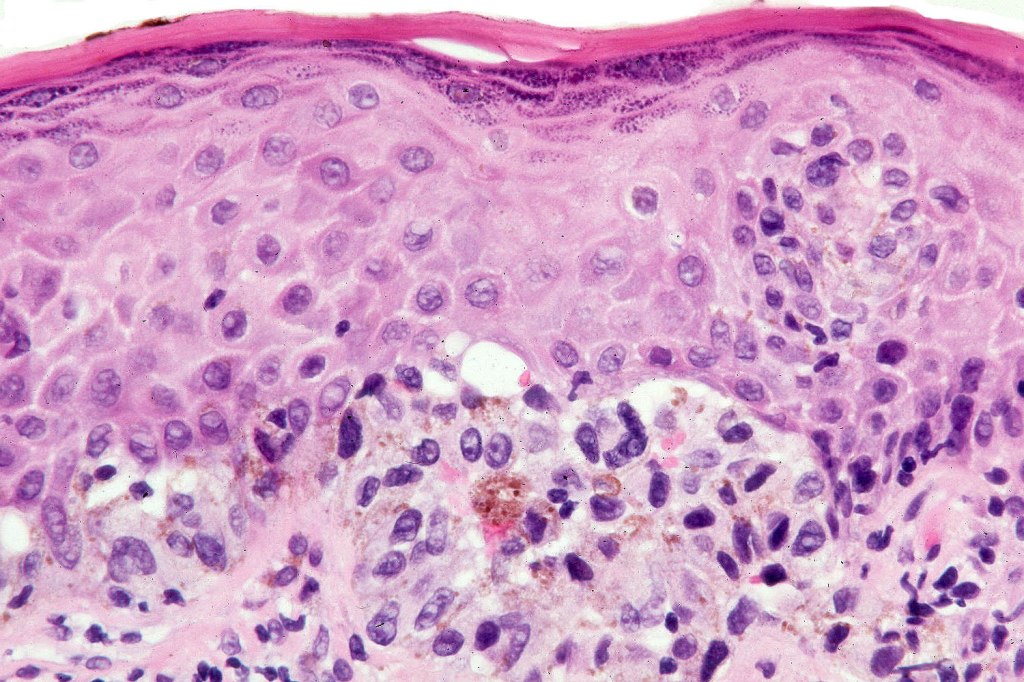

Histological features

•Large dyscohesive nests with retraction artifact, not restricted to the tips of the epidermal ridges

•Heavy pigmentation (sometimes gray/green)

•Variable atypia (can be marked)

•Superficial dermal atypia

. HMB45 shows gradation with depth, Ki67 is low